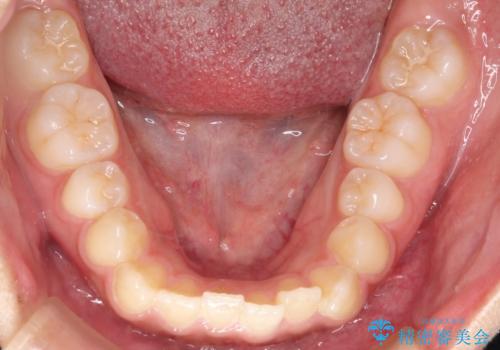

インビザライン 前歯のがたつきを目立たず矯正

- 前歯のがたつきが気になるとのことで来院されました。

インビザラインにて治療を行いました。

わずかに歯と歯の間に隙間を作り、歯列矯正を行いました。

マウスピースをしっかりと使用していただけたので、スムーズに治療を終了することができました。